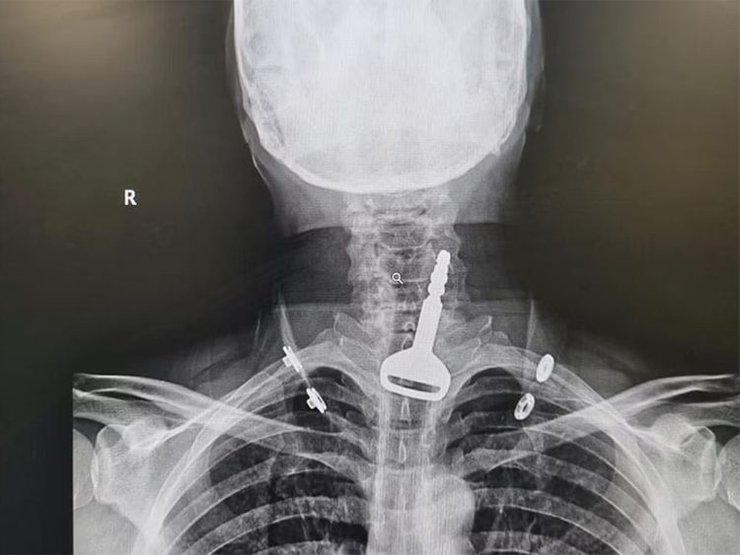

Издание Gulf News отмечает, что 49-летний мужчина поступил в приемное отделение больницы, где персонал заметил у него затрудненное дыхание. Рентгеновское обследование показало, что в дыхательных путях находится автомобильный ключ, и пациент рассказал врачам, что случайно проглотил его, когда играл с ним.

Фото: Sabq

Было принято решение о проведении эндоскопии для удаления ключа и устранения закупорки дыхательных путей, однако тот факт, что пациент был с больным сердцем, значительно усложнял процедуру.

К счастью, лапароскопическая операция прошла успешно, и ключ от автомобиля удалось извлечь. Пациент был госпитализирован на несколько дней, чтобы убедиться в отсутствии осложнений, но к настоящему времени он уже покинул больницу.